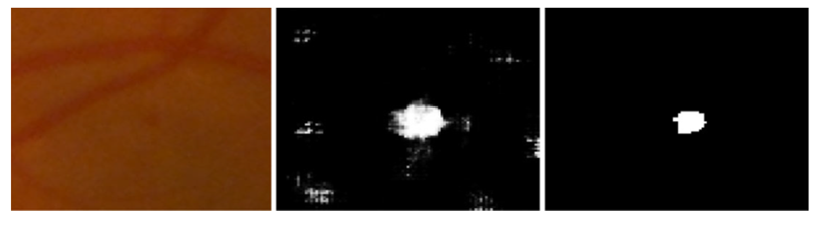

2.2. Data Pre-Processing

2.3. Patch Generation